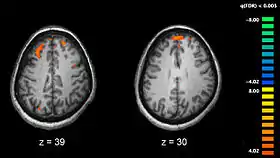

Schizophrenia has a fairly strong genetic component, although that is just one of a number of causes. Hypotheses for why schizophrenia emerges in some individuals but not others include an infection before birth, exposure to toxic substances, particularly drugs, and other disturbances of fetal development. Neurologically, there are some subtle but detectable differences in brains of people with schizophrenia. There is slight shrinkage in overall volume, and certain dopamine pathways also undergo chemical alterations.